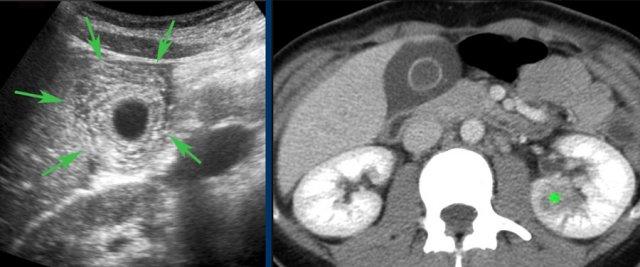

Hình ảnh siêu âm của một bệnh nhân bị phình to túi mật cấp tính, được khảo sát trên mặt phẳng dọc và mặt phẳng ngang.

Sỏi gây tắc nghẽn đang ở trạng thái kẹt (mũi tên).

Lưu ý rằng khi ấn đè, túi mật phình to phồng lên về phía thành bụng (đầu mũi tên), cho thấy áp lực trong lòng túi mật tăng cao.